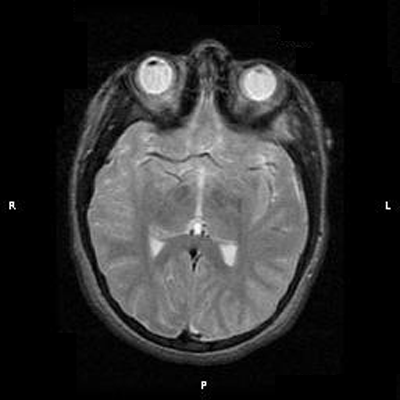

Clinical information: The patient was a 13 year-old girl who presented with worsening headache and some difficulties with memory, concentration and attention. MRI studies disclosed a 2.1 x 1.9 x 1.8 cm enhancing mass in the left temporal bone and sphenoid wing. The mass extended intracranially and abuts the left temporal bone accompanied by dural enhancement at that location. There is also extension through the bone into the submuscular temporal region. The following photos are taken from representative regions of the lesion. Panel 1 and 2 are CT scans at soft tissue and bone density respectively. Panel 3 and 4 are T1 weighed images without and with contrast respectively. Pandl 5 is proton density image. Panel A to D are cytologic (squash) prepartion for intra-operative consultation. Panel E and F are frozen sections for intraoperative consultation. Panel G to L are paraffin embedded sections.